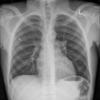

Normal PA Female

Date: 12/06/2014

Views: 6215